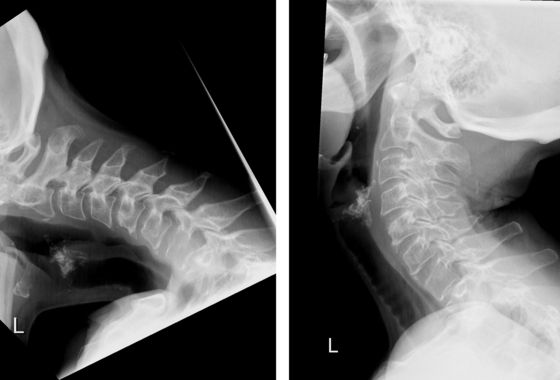

Dropped Head Syndrom (DHS), der «fallende Kopf», ist ein seltenes Leiden, das eine breite Differentialdiagnostik erfordert. Das DHS hat erhebliche Auswirkungen auf die Gesundheit und Lebensqualität der Betroffenen. Die Kopfhaltemuskulatur ist derart geschwächt, dass die Patientinnen und Patienten den Kopf nicht aufrecht halten können. Bisher war eine grosse Versteifungsoperation im Bereich der Hals- und Brustwirbelsäule die einzig mögliche Behandlung des DHS.

Prof. Mazda Farshad, Chefarzt und Direktor des Universitären Wirbelsäulenzentrums Zürich der Universitätsklinik Balgrist, und sein Team haben eine neuartige chirurgische Technik entwickelt, die erstmals eine erfolgreiche Behandlung des DHS ohne Versteifung ermöglichte. Mit der «Occipitopexy» genannten Methode wird der Kopf mit Ligamenten und Bändern an die Wirbelsäule befestigt. Der 68-jährigen Patientin geht es heute, eineinhalb Jahre nach der Operation, immer noch viel besser, sie lebt nahezu beschwerdefrei. Damit ist eine weniger einschneidende und vielversprechende Behandlung entstanden, die das Leiden der Patientinnen und Patienten lindert, ohne dass die Lebensqualität durch eine Versteifung beeinträchtigt ist.